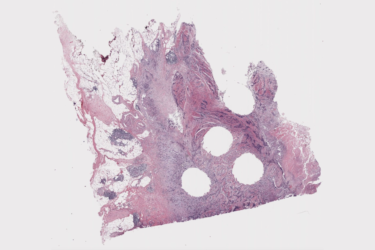

تتمحور عملية تفحص الجسم للعثور على السرطان وتشخيصه حول العثور على الأنماط. ويستخدم مختصو الصور الشعاعية الأشعة السينية والتصوير بالرنين…